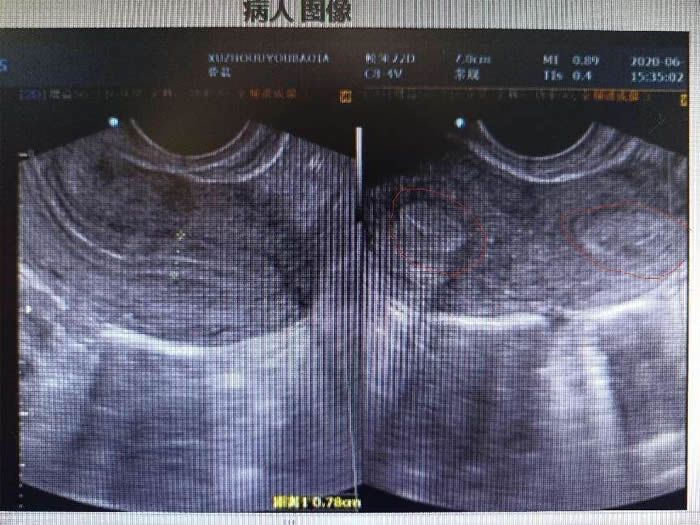

一年前,陳女士因為結(jié)婚兩年未孕、痛經(jīng)嚴重來到徐州市婦幼保健醫(yī)院就診。彩超檢查后發(fā)現(xiàn)陳女士子宮畸形,單角子宮合并殘角子宮II型,殘角子宮有功能內(nèi)膜,與單角子宮宮腔不相通,每次月經(jīng)經(jīng)血逆流導致陳女士腹痛難忍,日常還伴有同房的性交痛。